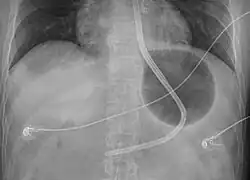

Preparation involves intubation followed by placing the person on their back at 45 degrees.[1] The device is then checked to make sure no leaks are present.[1] It is then placed via the mouth and 50 ml of air are added to the stomach balloon.[1] An X-ray is then done to verify placement and once confirmed more air is added.[1] Traction can then be applied.[1] Bleeding is then checked for, and if present the esophageal balloon may be inflated using a manometer.[1]

- Verify that the end of the tube is in the stomach by X-ray

- Inflate the stomach balloon with 250 to 500 ml depending on the type and apply traction.[6] This may be done by attaching a liter bag of normal saline over an intravenous pole.[3]